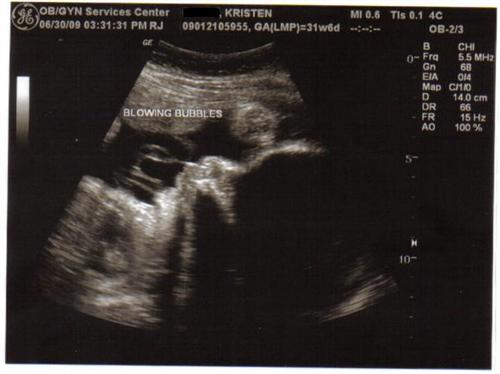

Our little boy is doing very well! He is measuing right on target for 31w6d 4.1lbs & head down!!! The tech said that he will be a 7-8lb baby if I go to term. His amniotic fluid is good but he is getting very cramped, so they would not be shocked to see me go early.

Here are 2 pictures that I love (we got about 8) & what made it so special is my mom got to accompany me & see her grandson in live time & it was her first time experiencing a sono!

HOW cute...blowing bubbles!

The bubbles picture is so cool!!!

How exciting!!! the blowing bubble pic!!!